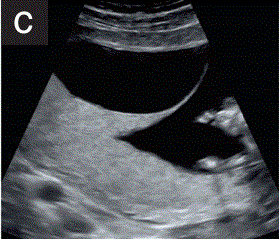

(2.4)在多胎妊娠中,应确定并记录绒毛膜和羊膜性(图2c)。

胎儿mt是什么检查什么疼吗【文献学习/规范指南】ISUOG实践指南(2023更新): 11-14周胎儿超声检查(全文)_https://www.jmylbn.com_新闻资讯_第8张

图2 11+0至14+0周时,可作为详细胎儿超声检查的一部分获得的解剖图。

(c)在多胎妊娠中,应通过寻求λ征(如双胎妊娠所示)或T来评估绒毛膜和羊膜。